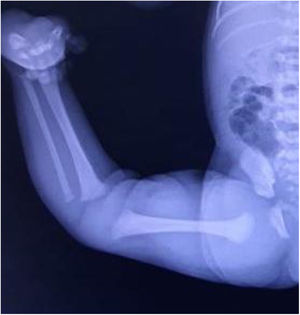

Congenital knee dislocation (CKD) is a very rare condition, with an estimated incidence rate of 1 per 100,000 live births,1 originally described by Chatelaine in 1822 and characterised by a genu recurvatum deformity present at birth (Figs. 1 and 2).

It can present in isolation or due to muscle imbalances in the context of other syndromes such as arthrogryposis, myelomeningocele or Larsen syndrome. It is frequently associated with other musculoskeletal anomalies such as hip dysplasia, clubfoot, congenital vertical talus and congenital dislocation of the elbow.2

Diagnosis is made soon after birth by physical examination, and plain radiography is helpful in some cases to establish level of severity.3

In the protocol described above, plain knee x-rays were not routinely performed, diagnosis in most cases being primarily clinical, as it is very difficult to take radiographs with pure projections in this type of patient (Fig. 4). “Continuous" fluoroscopy was used during cast immobilisation.